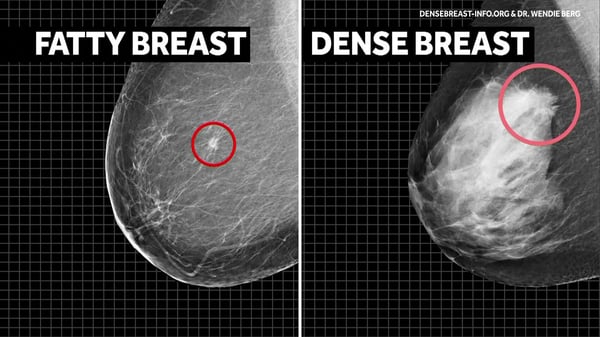

On a mammogram, fatty breast tissue appears dark, making tumors (white areas) easier to see. In dense breasts, both normal tissue and tumors look white, which can hide cancers and make them harder to detect.

Dense breast tissue can “mask” tumors on a mammogram, reducing detection rates significantly. Breast Ultrasound should be used in conjunction with mammography.

Almost half of American women have dense breasts, which can hide abnormalities on mammograms. Ultrasound “sees” through dense tissue, boosting detection accuracy.